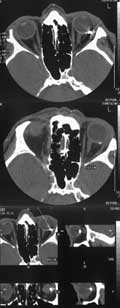

Для уточнения локализации инородных тел при осложненных ранениях глаз нами применяется компьютерная томография. Исследование было проведено 72 больным, из них у 15 были установлены сквозные ранения глазного яблока; у 54 больных инородные тела локализовались в оболочках заднего полюса глаза. Сроки поступления больных в Республиканский Центр реконструктивной микрохирургии глаза варьировали от 1–2 месяцев — 26 больных; 3-6 месяцев — 17 больных; 1 год — 7 больных; 2 года — 2 больных; 4 года — 1 больной, 14 лет — 1 больной. Причинами столь позднего обращения к нам пациентов с внутриглазными инородными телами были следующими: 1) отсутствие возможности проведения рентгеновской компьютерной томографии перед проведением первичной хирургической обработки; 2) недостаточное техническое оснащение операционной; 3) отсутствие витреоретинального хирурга при первичной хирургической обработке; 4) неправильное определение магнитных свойств внутриглазного инородного тела. До операции все больные обследовались по общепринятой схеме с обязательным проведением рентгеновской компьютерной томографии, ультразвукового сканирования. Рентгеновская компьютерная томография нами применена у всех 54 больных с локализацией ВИТ в оболочках заднего полюса (Рис. 1). Использовали компьютерный томограф “Somatom-DR-H“ фирмы “Simens“. Основные технические характеристики: матрица 512х512, толщина среза 2–4 мм, время сканирования 7 с, количество срезов 10–15. Сканирование проводили в аксиальной плоскости под углом 12–15°. Для более прицельного изучения структур орбиты, их дифференциации, изображение интересующей зоны увеличивали в 2–4 раза. На основании полученных данных широко использовали реконструкции изображения в различных заданных плоскостях для получения наибольшего объема информации. Анализировались состояние костных стенок орбиты, мышц глаза, зрительного нерва, величина и форма глазного яблока. Для определения плотности инородного тела использовали шкалу Хаунсфилда.

[Увеличить]

Рис. 1. Компьютерная томограмма. Инородное тело в оболочках заднего полюса глазного яблока.